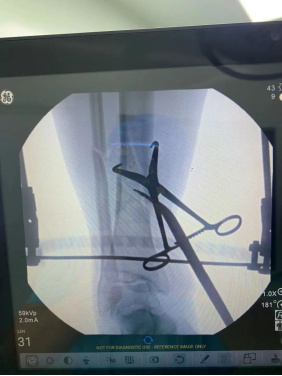

【胫腓骨骨折 】

(术者:CO接骨专家史医师)

【术中手术图】